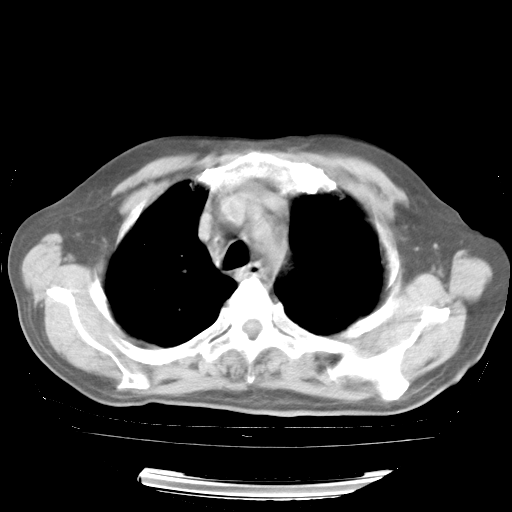

4月28日肺部CT——再次出现类似去年5月9日——透光度降低,“间质性”改变。

4月28日肺部CT——再次出现类似去年5月9日——磨玻璃样、间有“粟粒样”改变。